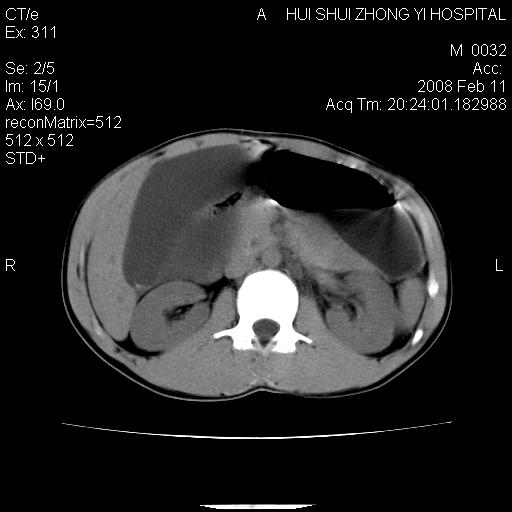

标题: CT11660:男,16岁,现腹痛剧烈,现发烧、头痛、恶心呕吐 [打印本页]

标题: CT11660:男,16岁,现腹痛剧烈,现发烧、头痛、恶心呕吐

8年前曾在贵洲省人民医院b超诊断为肝内胆管结石。现腹痛剧烈,现发烧、头痛、恶心呕吐县医院b超示胆囊肿大大小159*46mm,囊内见6*5mm强回声光团,胆各总管内径56mm。提示:胆囊结石、急性胆囊炎、胆总管重度扩张。

胆囊结石.急性胆囊炎.重度胆管扩张.右侧胸腔少量积液,建议ct增强

考虑先天性胆管囊肿;胆囊增大并结石。右侧胸腔少量积液,建议ct增强。

caroli囊肿并囊内结石。胆囊增大并胆结石。典型!

先天性胆管囊肿,胆囊结石、胆囊增大,右侧少量胸腔积液。